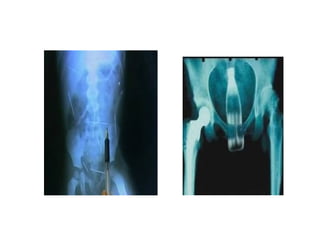

IMAGENS DE RADIOLOGIA

CONVENCIONAL